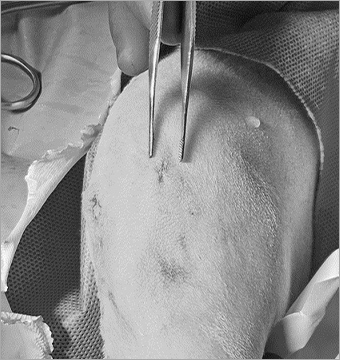

최소절개 TPLO 수술

예은동물의료센터에서는 근육・힘줄을 최대한 보존하는 최소 침습 TPLO 수술 시행하며

관절경을 통해 관절을 열지 않고 수술을 진행하기때문에 환자의 통증을 최소화합니다.

소형견

대형견